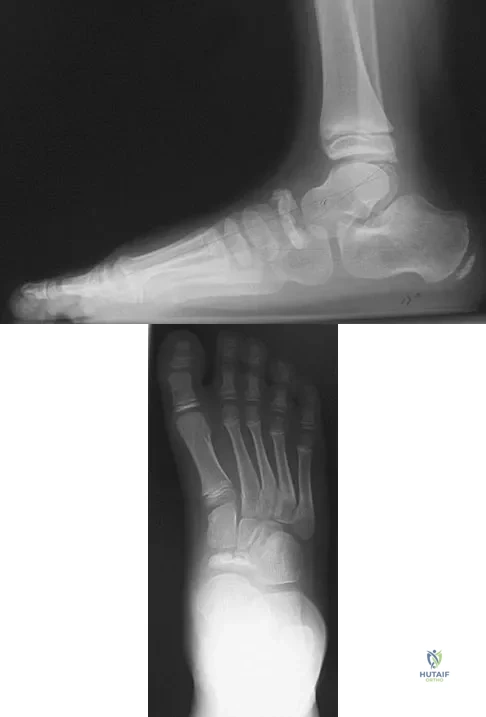

Figures 9a and 9b show the radiographs of a 28-year-old woman who sustained a head injury and a closed injury, without soft-tissue compromise, to her right lower extremity in a motor vehicle accident. Appropriate management of the foot injury should include

A 9-year-old boy has pain over the midfoot medially with activity. Based on the findings shown in Figures 26a and 26b, which of the following is considered the most effective short-term management?